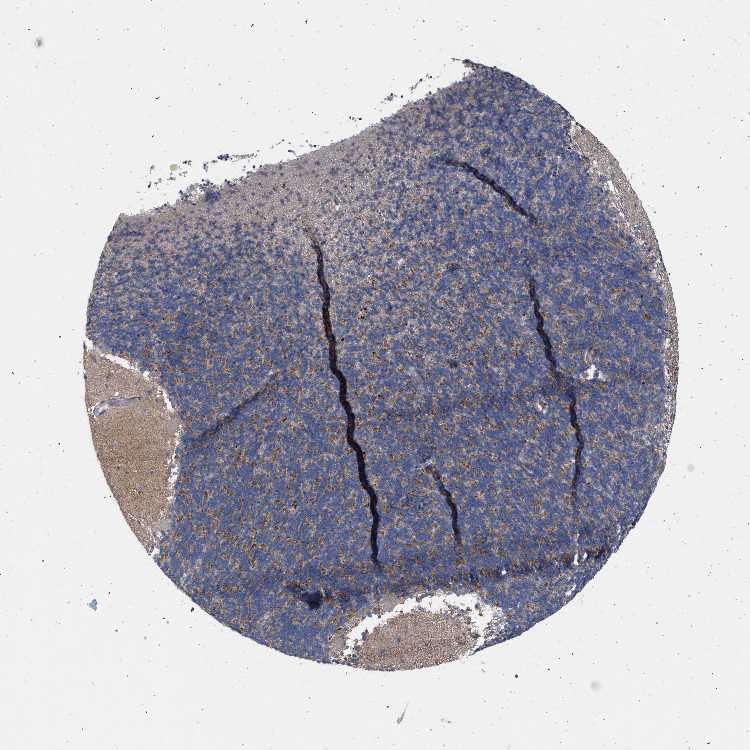

CEREBELLUM - Antibody stainingi

Antibody staining in the annotated cell types in the current human tissue is reported as not detected, low, medium, or high, based on conventional immunohistochemistry profiling in selected tissues. This score is based on the combination of the staining intensity and fraction of stained cells.

Each image is clickable and will lead to virtual microscopy that enables deeper exploration of all samples and also displays staining intensity scores, fraction scores and subcellular localization as well as patient and tissue information for each sample.

Antibody HPA021814Antibody HPA022249

Purkinje cells Not detectedNot detected

Cells in granular layer MediumNot detected

Cells in molecular layer LowNot detected